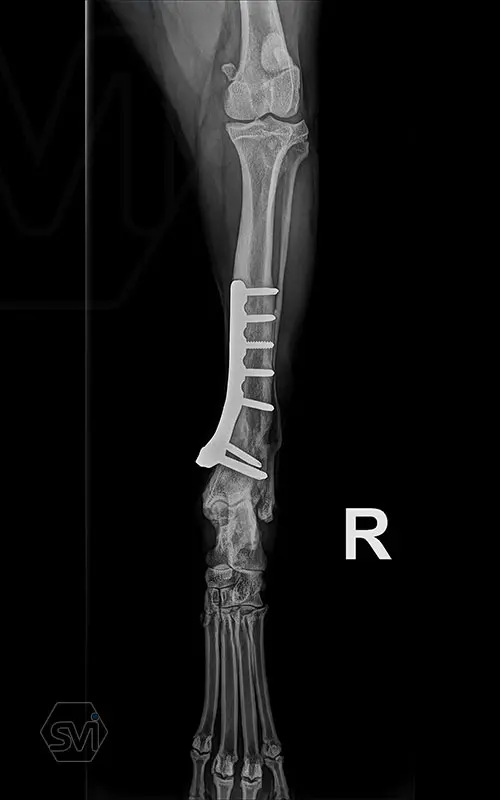

Multifunctional symmetrical long polyaxial locking plate - designed for the treatment of fractures close to joints

A special member of the polyaxial locking plate family is the multifunctional long plate, which is an extended version of the well-known symmetrical TPLO plate, with a 5-3 hole distribution. The plate also received a DCP hole to be able to create compression, and there is a mini-hole on the head end to facilitate the placement of the temporarily used K-nail. The burrs on the side facing the bone surface are intended to reduce the contact surface between the plate and the bone (limited contact).

The plate is a member of the large polyaxial locking family, suitable for 2.7-3.5-4.0 mm screws. We recommend it for fixaton of fractures close to joints, wedge osteotomies with axis correction (closing and opening), or for CWTO operations.